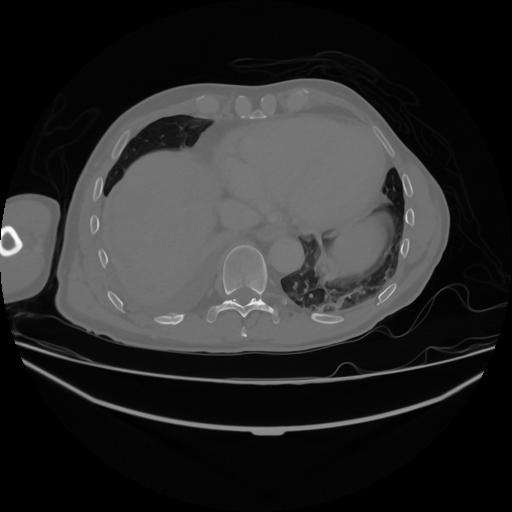

5 CUERPO,CE,Vol,1.0,CUERPO,,